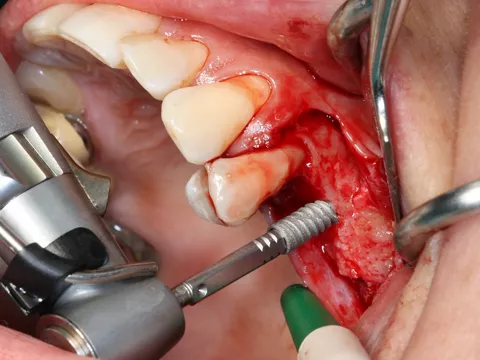

9-10-11. The patient had D3 bone density. Hence an undersized drilling protocol was employed, the final drill diameter being one less than that of the implant. The green drill was used for the 25 implant (diameter 3.4) and the red one for the 26 (diameter 4.0).

9

10

11

12a-b-c. The design of the Axiom X3® ensures atraumatic implant placement with the micro motor. The Axiom X3® also preserves bone, even if the ridge is thin and resorbed. Despite the meager quantity of vestibular cortical bone, there was no perforation or rupture of the crestal margin.

13. The implants were placed 0.5–1 mm subcrestally. Note the thinness of the vestibular cortical bone at the 25 implant on this occlusal view. Despite this, we achieved perfectly acceptable stability values of 19 and 20 Ncm.